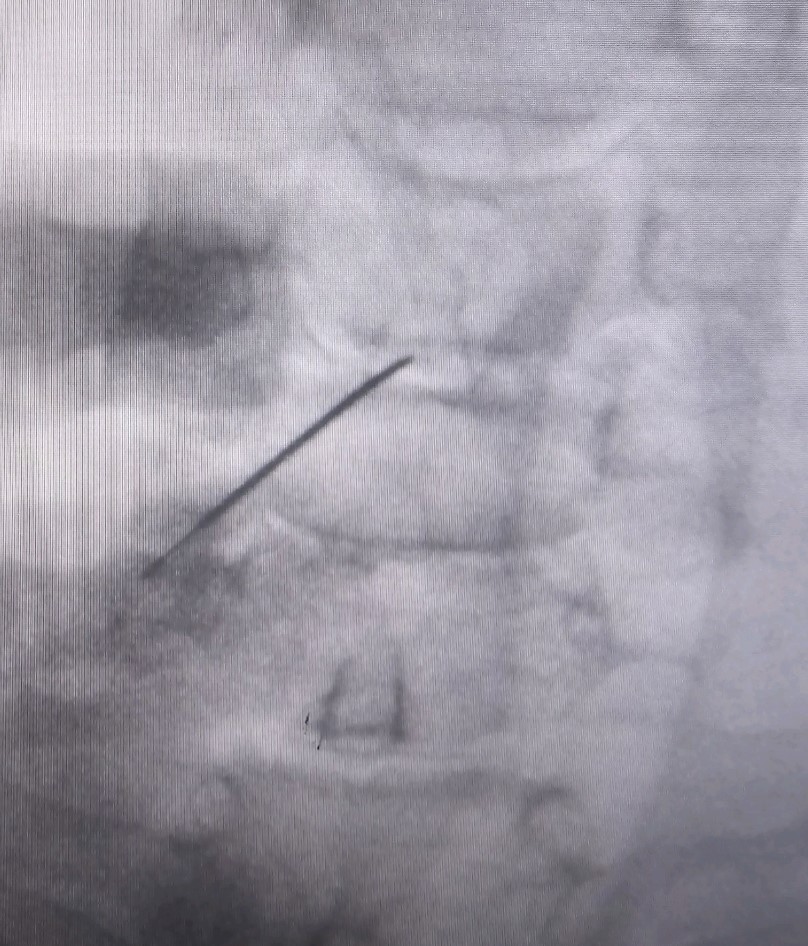

Η επέμβαση γίνεται κάτω από συνεχή ακτινοσκοπική καθοδήγηση με τον ασθενή σε πρηνή θέση και ήπια καταστολή. Εισάγεται μια ειδική βελόνη στον δίσκο και μέσω αυτής εισέρχεται ένας ειδικός καθετήρας που συνδέεται με τη γεννήτρια του μηχανήματος που χορηγεί την ενέργεια. η επερχόμενη μείωση της ενδοδισκικής πίεσης, προκαλεί την υποχώρηση της κήλης προς το κέντρο του δίσκου, μειώνοντας έτσι την πίεση της σύστοιχης νευρικής ρίζας. Σε μια επέμβαση δύναται να αντιμετωπισθούν έως και 3 επίπεδα δίσκου.

Η τεχνική εφαρμόζεται στην αυχενική μοίρα της σπονδυλικής στήλης με πρόσθια προσπέλαση και στην οσφυϊκή μοίρα με οπίσθια προσπέλαση, κάτω από ακτινοσκοπική καθοδήγηση και με χρήση σκιαγραφικής ουσίας για την απεικόνιση του δίσκου πριν την έναρξη της εξάχνωσης.